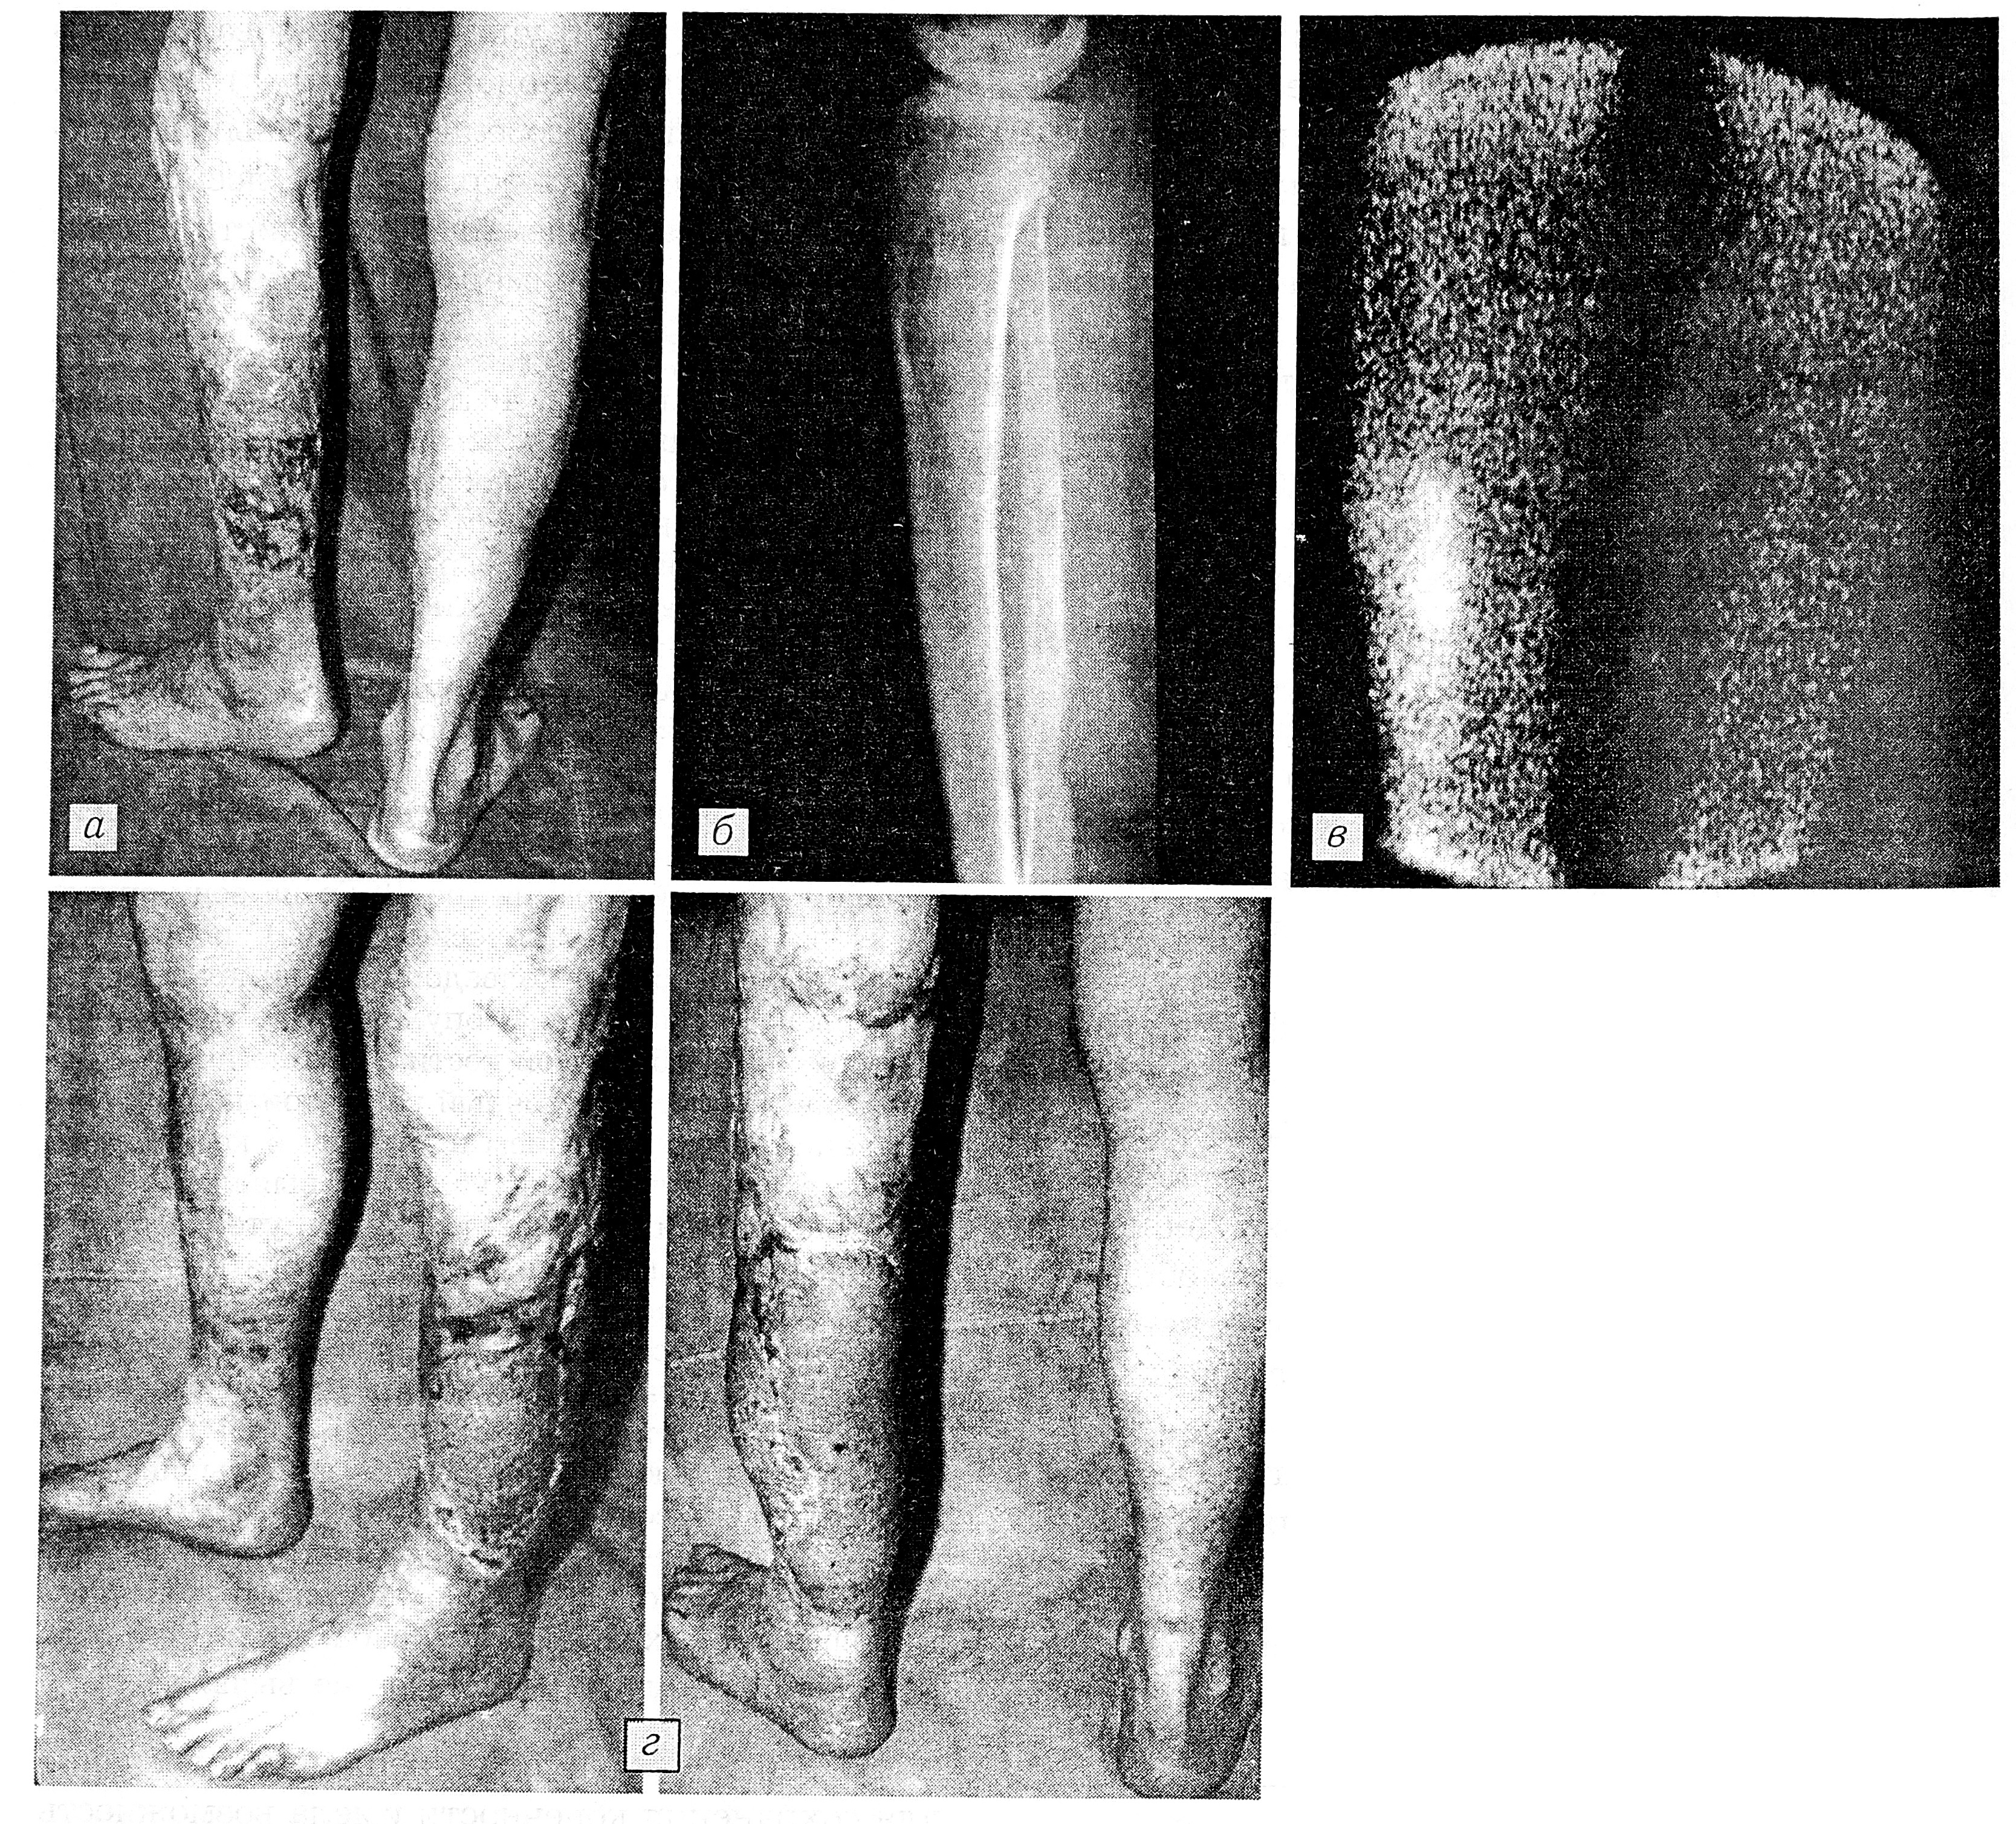

Больной М-в, 46 лет, поступил с плоскоклеточным раком кожи левой голени (T4N1M0) на месте обширного рубца после термического ожога. Площадь поражения кожи 20×20 см (рис. 1, а). При рентгенологическом и радионуклидном исследовании выявлено поражение малоберцовой кости (рис. 1, б, в). В случае ампутации протезирование было бы чрезвычайно затруднено из-за наличия грубых послеожоговых рубцов, которые занимали всю конечность до ягодичной складки. При обследовании обнаружены увеличенные лимфатические узлы в паховой области. Проведен курс предоперационной лучевой терапии (по 40 гр на зону опухоли и паховые лимфатические узлы), после чего произведены пахово-подвздошная лимфаденэктомия слева и иссечение опухоли с сегментарной резекцией малоберцовой кости. Гистологическое исследование: плоскоклеточный рак с признаками ороговевания с прорастанием в мышцы и кость; метастазов в лимфатических узлах не выявлено.

Образовавшийся дефект закрыт путем пересадки лопаточного кожного лоскута и фрагмента зубчатой мышцы на раздельных сосудистых ножках с закрытием поверхности мышцы расщепленным кожным трансплантатом. Сосудистая ножка лопаточного лоскута вшита в задний сосудистый пучок по типу конец в бок, фрагмента зубчатой мышцы — в малоберцовый сосудистый пучок по типу конец в конец. Послеоперационный период протекал без осложнений (рис. 1, г). Опороспособность конечности полностью сохранена. Срок наблюдения — 3 года. Рецидива опухоли и метастазов не выявлено.

Рис. 1. Больной М-в. Плоскоклеточный рак кожи на месте послеожогового рубца. а — внешний вид, б — рентгенограмма левой голени, в — сцинтиграмма до операции: костная деструкция (б) и повышенное накопление радиофармпрепарата (в) подтверждают прорастание опухоли в малоберцовую кость; г — после операции (вид сбоку и сзади).